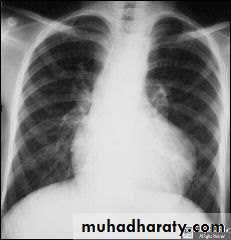

• CXR : boat shaped heart , clear lung field , 20 % right sided aorta .• ECG : RVH , right axis deviation .